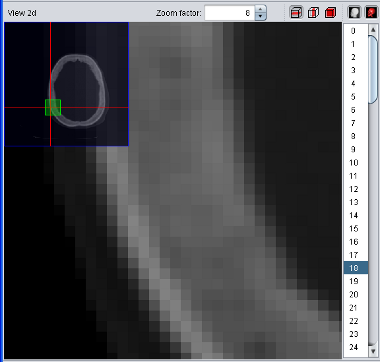

The temporary selection is always drawn in red. For example, if you have a blue segment wich overlaps with the current selection, the overlapping region will be drawn in purple since red + blue = purple. To make things easier to see, a simple geometric shaped blue segment is used (sphere) and the temorary segment/selection is shaped like a small red box.

|

| Selection (red) and segment (blue) |